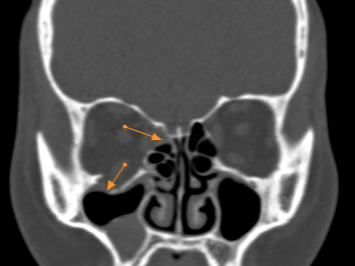

图片

图3.图中箭头提示传统手术修复材料大小和形状均不合适